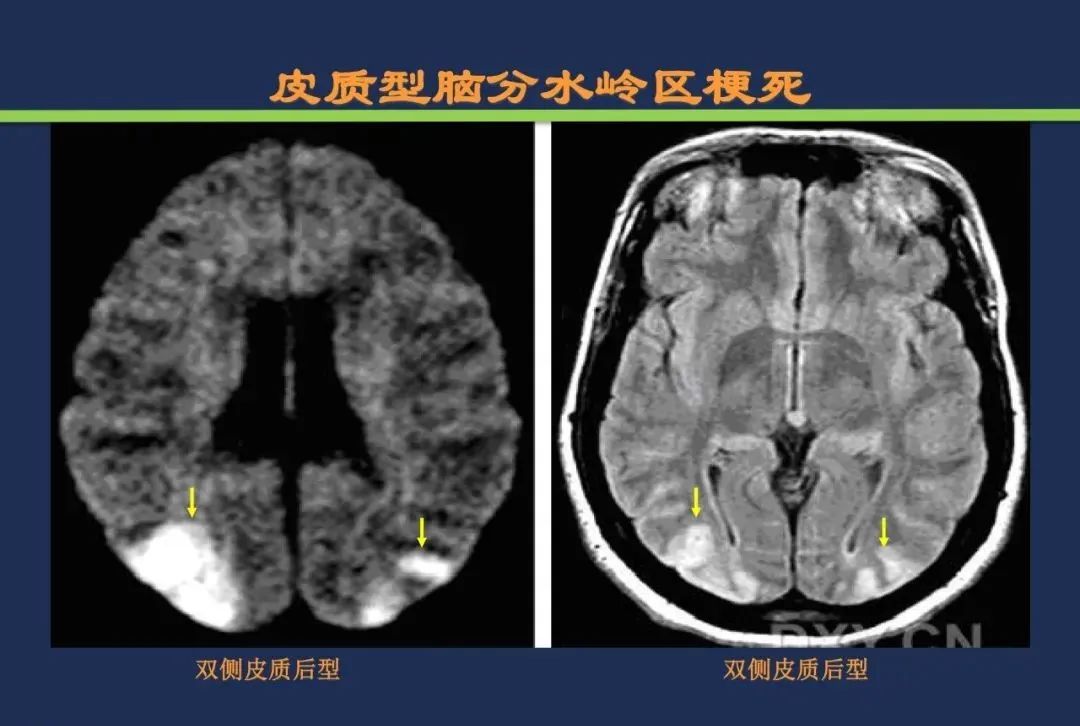

分水岭梗死皮质前型+皮质后型+后上型皮质下前型+皮质下后型+皮质下上型+皮质下外型+皮质下下型